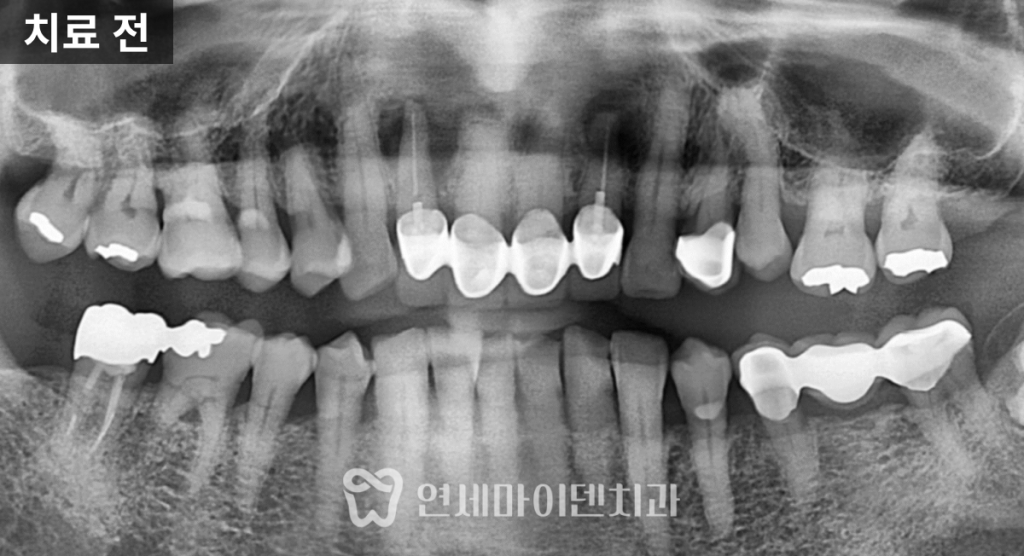

정밀 촬영 결과

두 개의 앞니 뿌리 끝, 즉 치근단 부위에서

뚜렷한 염증 소견이 확인되었습니다.한쪽 치아는

뼈 손상이 심해 예후가 불량한 상태였고,

다른 한쪽은

염증이 국소적으로 제한되어 있어

신경치료 후 경과를 지켜볼 수 있는 상황이었습니다.이에 따라 치료 계획은 다음과 같이 세웠습니다.